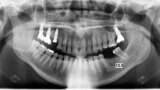

Conventional and immediate loading with final n!ce screw-retained crowns